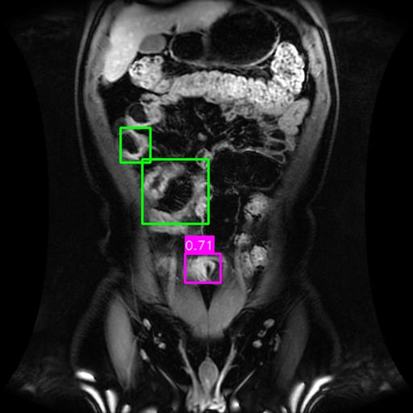

(a) Mask R-CNN [He2017MaskRCNN]

Refer to caption

(b) DiffusionDet [Chen2023DiffusionDet_ICCV]

(c) DeFloMat (Ours)

Figure 3: Qualitative Comparison on Crohn’s Disease MRE Test Set. The figure compares detection results from (a) Mask R-CNN, (b) DiffusionDet (S=3S=3), and (c) DeFloMat (Ours, S=3S=3) on challenging MRE slices. Green boxes indicate True Positives (TP, IoU 0.1\geq 0.1), Red boxes indicate False Positives (FP), and Purple boxes indicate False Negatives (FN). DeFloMat consistently demonstrates superior localization quality and sensitivity: it successfully detects subtle inflammation regions (TP) that are often missed (FN, Purple boxes) by the Mask R-CNN baseline (Row 2, 4). Furthermore, DeFloMat provides tighter bounding box localization compared to DiffusionDet, confirming the benefit of learning the direct, deterministic flow field. The results show DeFloMat’s robustness in capturing varying sizes and numbers of inflammatory lesions.

Qualitative Assessment.

Figure 3 provides visual evidence of the models’ performance on challenging MRE slices, where inflammatory lesions can be subtle or obscured. The qualitative results underscore DeFloMat’s enhanced localization fidelity. In challenging cases (e.g., Row 2 and 4), Mask R-CNN and DiffusionDet frequently produce False Negatives (FN, Purple boxes), failing to detect clear inflammation sites. In contrast, DeFloMat reliably converts these FNs into True Positives (TP, Green boxes) by providing tighter and more accurate bounding box predictions. This suggests that the deterministic velocity field learned via Flow Matching is highly effective at precisely directing the proposal centers towards the true lesion locations, a characteristic that is vital for accurate clinical reporting. DeFloMat’s ability to achieve such precise localization with only S=3S=3 steps highlights its clinical utility for rapid diagnostic auxiliary systems.